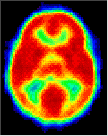

Click on image above to view full-size image.

The high CMRGlc during 3 to 10 years corresponds to the period of exuberant connectivity in humans and is probably required to meet the energy demands of the neuronal processes and synapses that are also in excess by about a factor of two compared to adults. Shown above are PET scans from 3 different ages showing the relative glucose metabolic rate. Beneath the PET scans are drawings showing the relative complexity of the dendritic structure of cortical neurons. The progressive increase in glucose utilization seen in development is consistent with anatomical studies showing an expansion of dendritic fields (and synaptic connectivity) and an increase in capillary density in the human frontal cortex during the same period. Thus, it is possible that the decrease in glucose metabolic rate in the adult reflects a "pruning" of excessive neuronal connectivity and a selective stabilization of the remaining neuronal connections.